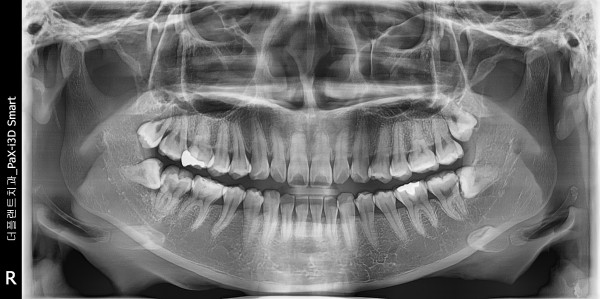

사랑니 | 사랑니 발치(#18,48)

#18,48 마취 후 사랑니 발거 시행하였습니다

•치료명 : 하악 매복사랑니 발거

•치료기간 : 하루